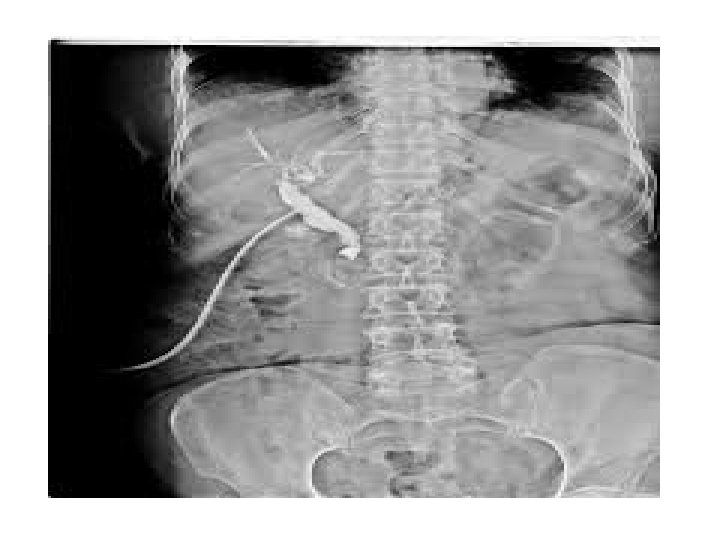

OPERATIVE CHOLANGIOGRAPHY In an intraoperative cholangiogram, image of bile ducts is taking during a surgical procedure, a catheter is inserted into the bile duct and technician injects contrast medium directly into the biliary tract that will highlight the bile ducts. It is helpful prior to surgery and reduce the risk of complications. It is cost effective also. It also helps the surgeon get oriented and can reduce the risk of injury to the bile ducts.

Surgeons may request an intraoperative cholangiogram in any procedure when they will be working with or around the bile ducts, particularly in a cholecystectomy, where the practitioner removes the gallbladder. These procedures are often performed endoscopically, with the use of tools inserted through small incisions and guided by a camera.

In the intraoperative cholangiogram, a technician injects a contrast medium that will highlight the bile ducts on an x-ray. Once the medium has a chance to circulate, a series of images can be taken to watch it move through the bile ducts. The resulting images highlight the anatomical structures in the area and provide important information for the surgeon about the location of the common bile duct. If there is a problem as a result of surgery, the surgeon can look for indications of potential trouble, which might include leaking contrast medium or an area of obstruction

When a surgeon recommends a gallbladder removal or other surgery in this area, this may include a request for an intraoperative cholangiogram. Information about the test can be provided to the patient along with other material about the surgery. Surgeons thus take reasonable precautions to reduce the risk of complications and identify surgical errors as quickly as possible. Procedure takes around 15 -20 min.